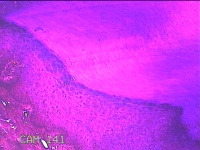

性别

女

年龄

61岁

临床诊断

鸡眼

一般病史

发现左足结节,伴局部疼痛不适2年余。

标本名称

左足结节

大体所见

灰白暗红色带皮肤样结节2.3x1.2x0.3cm一个,表面糜烂,切开结节呈实性,切面灰白暗红色,质硬。